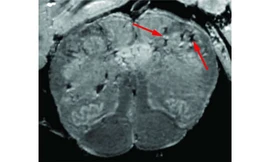

TPO - Trong một nghiên cứu chuyên sâu về cách COVID-19 ảnh hưởng đến não của bệnh nhân, các nhà nghiên cứu của Viện Y tế Quốc gia Mỹ đã liên tục phát hiện ra các dấu hiệu tổn thương do mạch máu não mỏng và bị rò rỉ trong các mẫu mô của những bệnh nhân chết ngay sau khi mắc bệnh.